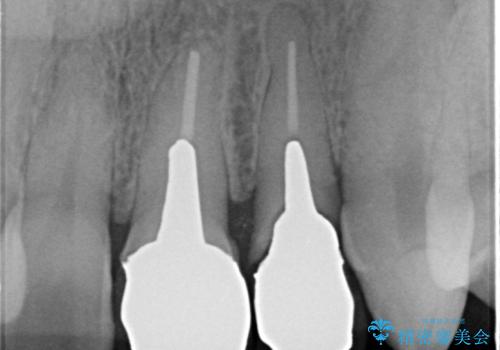

X線撮影や歯周組織検査から、クラウン下の虫歯の再発や歯の破折が疑われる状況でした。

左上2は、クラウン メタルコアの除去を行ったところ虫歯の再発や亀裂を認め、長期的な予後の期待が難しいことから抜歯を行い